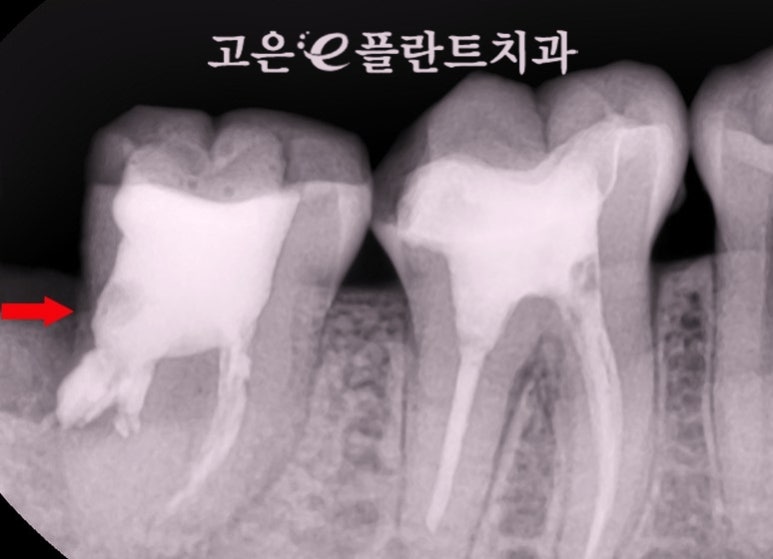

사진으로 보다 싶이

옆쪽이 깨져나갔습니다.

신경치료를 받은 이는

고목나무와도 같은 상태가 됩니다.

그 상태로 씌우지 않고

방치하게 된다면 결국에는

이렇게 깨져 나가게 되는거죠.

치조골의 상태를 파악하기 위해

엑스레이 사진을 찍어보았습니다.

사진상으로 염증조직이 상당해보였는데요,

이로 인해 치조골이

많이 소실 된 상태였습니다.